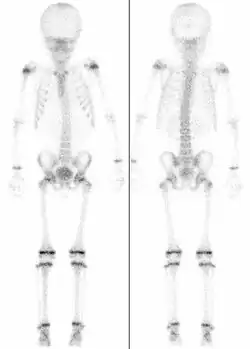

Chrząstka nasadowa (łac. cartilago epiphysialis), tworząca płytkę nasadową, inaczej płytkę wzrostu – tkanka chrzęstna znajdująca się w pobliżu zakończeń rosnącej kości. Jest to miejsce wzrostu kości na długość. W trakcie wzrastania pojawiają się w niej kolejne punkty kostnienia, by po zakończonym wzroście chrząstka ta całkowicie przekształciła się w kość. Po zaniku chrząstki nasadowej pozostaje ślad w postaci podwójnej blaszki kostnej, kresa albo linia nasadowa (łac. linea epiphysialis). Proces zaniku chrząstek nasadowych ustaje u kobiet około 16-18. roku życia, zaś u mężczyzn około 20-21. roku życia. Część trzonu sąsiadującą z chrząstką nasadową nazywamy przynasadą (metaphysis).